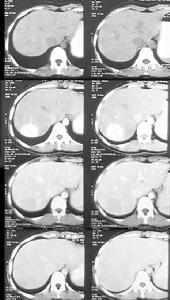

2.CT平掃 腫瘤呈低密度區,增強後可顯示不同密度增強CT示腺瘤一般為等密度或輕度低密度因腺瘤富含血管在造影的動脈期獲得CT影像更容易發現腺瘤。伴有糖原累積病或其他致脂肪浸潤的病人,腫瘤可以表現為高密度。中心壞死鈣化偶爾也很明顯。腫瘤內出血在非增強CT檢查上表現為高密度靜脈造影后腫瘤增強多不均一